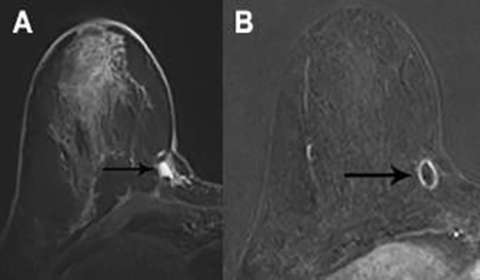

A fluid- or blood-filled cavity following lumpectomy is a normal finding. Seromas are typically T2 hyperintense with smooth, thin rim enhancement (Figure 2a).1 Nodular enhancement greater than 5mm is concerning for residual disease (Figure 2b). A seroma with typical imaging features is a benign finding (BI-RADS 2).